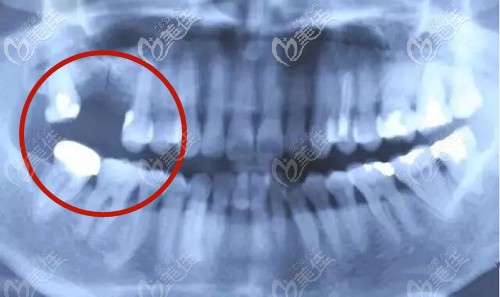

鄭州金水春芽口腔門診部

人氣 0.2 活躍 6.8 診療科目 口腔科 //醫(yī)學影像科 | X線診斷專業(yè)(限口腔)******